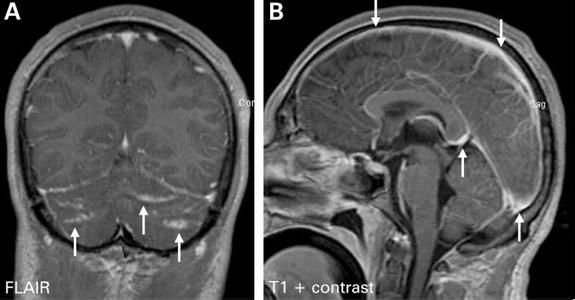

隐球菌感染的临床表现多种多样,可以包括从无症状、局限性肺部感染到播散性疾病。播散性疾病可以累及机体任何系统,最常侵犯中枢神经系统导致脑膜炎、脑膜脑炎及颅内局灶性肉芽肿。

脑膜脑炎的典型表现为严重头痛,可持续数周至数月,可伴随精神状态改变、人格改变、发热、昏睡及昏迷;其他神经系统并发症包括脑积水(交通性或非交通性)、视乳头水肿、突发感音性聋、颅神经麻痹、运动感觉障碍、小脑功能障碍和癫痫等。